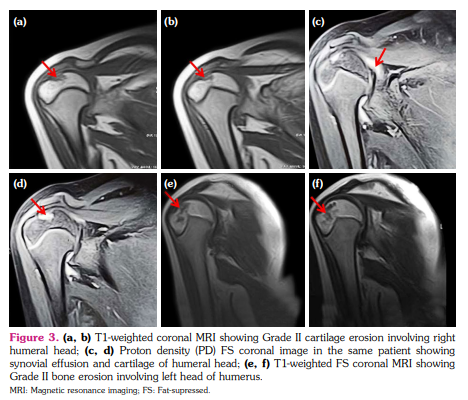

a) Synovial hypertrophy score: Thirteen (40.6%) joints in nine patients revealed synovial hypertrophy with a mean grade score of 0.7±0.9 (Figure 1 a, b). Five joints had Grade I and eight joints had Grade II synovial hypertrophy (Figure 2a). The number of joints with synovial hypertrophy in sJIA, ERA, and undifferentiated JIA were seven (53.8%), four (30.7%), and two (15.3%) joints, respectively.

b) BME score: Twenty-one (65.6%) joints in 13 patients revealed BME with a mean grade score of 1.1±1.0 (Figure 1c, d). The number of joints which had Grade I, II and III BME scores were 11, seven, and three, respectively (Figure 2a). The number of joints with BME in sJIA, ERA, and undifferentiated JIA was 13 (61.9%), five (23.8%), and three (14.2%) joints, respectively. Of these 21 joints, only two joints revealed BME with no other findings and the rest 19 joints showed synovial effusion or one or the other MRI parameter of joint inflammation. There was no statistically significant difference in the occurrence of BME in sJIA subset versus the rest of the JIA subsets (p=0.823).

c) Cartilage lesion score: Nine (28.1%) joints in six patients showed cartilage lesions with a mean score of 0.3±0.6 (Figure 3a-d). Seven of these joints had Grade I and II joints had Grade II cartilage lesions (Figure 2a). The number of joints with cartilage lesions in sJIA and undifferentiated JIA were six (66.6%) and three (33.3%), respectively.

d) Bone erosion score: Bone erosions were seen in 15 (46.8%) joints in nine patients with a mean score of 0.6±0.8 (Figure 3e, f). Eleven joints had Grade I, three had Grade II, and one joint had Grade III bone erosion score (Figure 2a). The number of joints with bone erosions in sJIA, ERA, and undifferentiated JIA were 11 (73.3%), three (20%), and one (6.7%) joint, respectively.